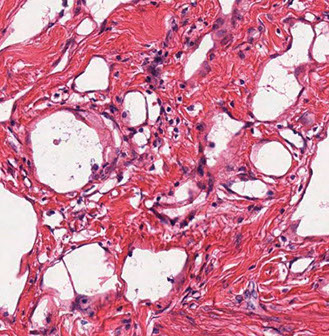

Serous carcinoma

1/10 em ca, mod to marked atypia in papilary, glandular or solid patterns

- assoc c atrophic endometrium and not with hormone exposure seen in older black women; may be assoc c some tx's (chemo-rads) and other gyn ca's

Micro: looks and acts like serous ca of the ovaries (aka papillary serous ca), with papillae having lining cells c lots of atypia with multinucleation, "lobster-claw" branching, detachment of cancer cells into luminal spaces, cytoplasmic vacuolization, hobnail cells

-psammoma bodies common

Px: assoc c myometrial and vascular invasion, and is often spread out of uterus at dx

- can be cured if there isn't any extrauterine spread (4/5 survival), otherwise will come back and kill pt; very aggressive

- not graded bc all are considered high grade

IHC: (+) p53 (either strong and diffuse or completely negative ["null" phenotype]),  p16 (strong, diffuse pos), ER/PR (1/2+, ER weak and patchy) CK7, CA125, very high Ki67, ER/PR (either ER+/PR+ or ER+/PR-, and can be weak and patchy), HER2/neu (in 1/3, usually lateral/basolateral with lack of staining in the apical portion of the cell membrane)

- negative: WT1 (but is pos in ovarian serous ca), CEA, CK20, HNF-1beta

- up to 90% of cases has p53 mutations, which correlates with abnormal p53 expression by IHC

- usually p53 has diffuse and strong nculear staining in >75% of tumor cells (only 10% of serous EACs show complete absence of p53 immunoreactivity due to nonsense mutations or homozygous gene deletion

- p53 mutation is an early event in serous carcinogenesis

Genes: TP53 mutations well characterized alteration in most cases